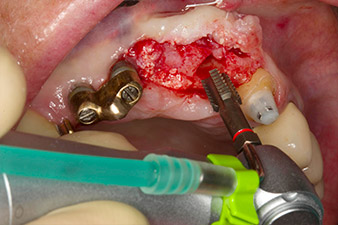

След първичното оздравяване, меките тъкани са оформени посредством базално разположения мост. Два месеца по-късно, обработваното поле е изложено на палатинална алвеоларна инцизия (Фиг 2). Размерите на алвеоларната кост са достатъчни в позиция 22. Фигури 2 и 4 показват препарацията на имплантното ложе, нарязващия винт и имплатирането, използвайки Implantmed.

Новият имплантологичен мотор е използван с подходящите обратни наконечници на W&H.

С цел да се компенсира периодонталната загуба на кост и да се постигне естетически добър резултат, имплантирането е комбинирано с водена костна регенерация (GBR) с ксеногенен заместващ материал и колагенова мембрана (Фиг. 5 и 6).